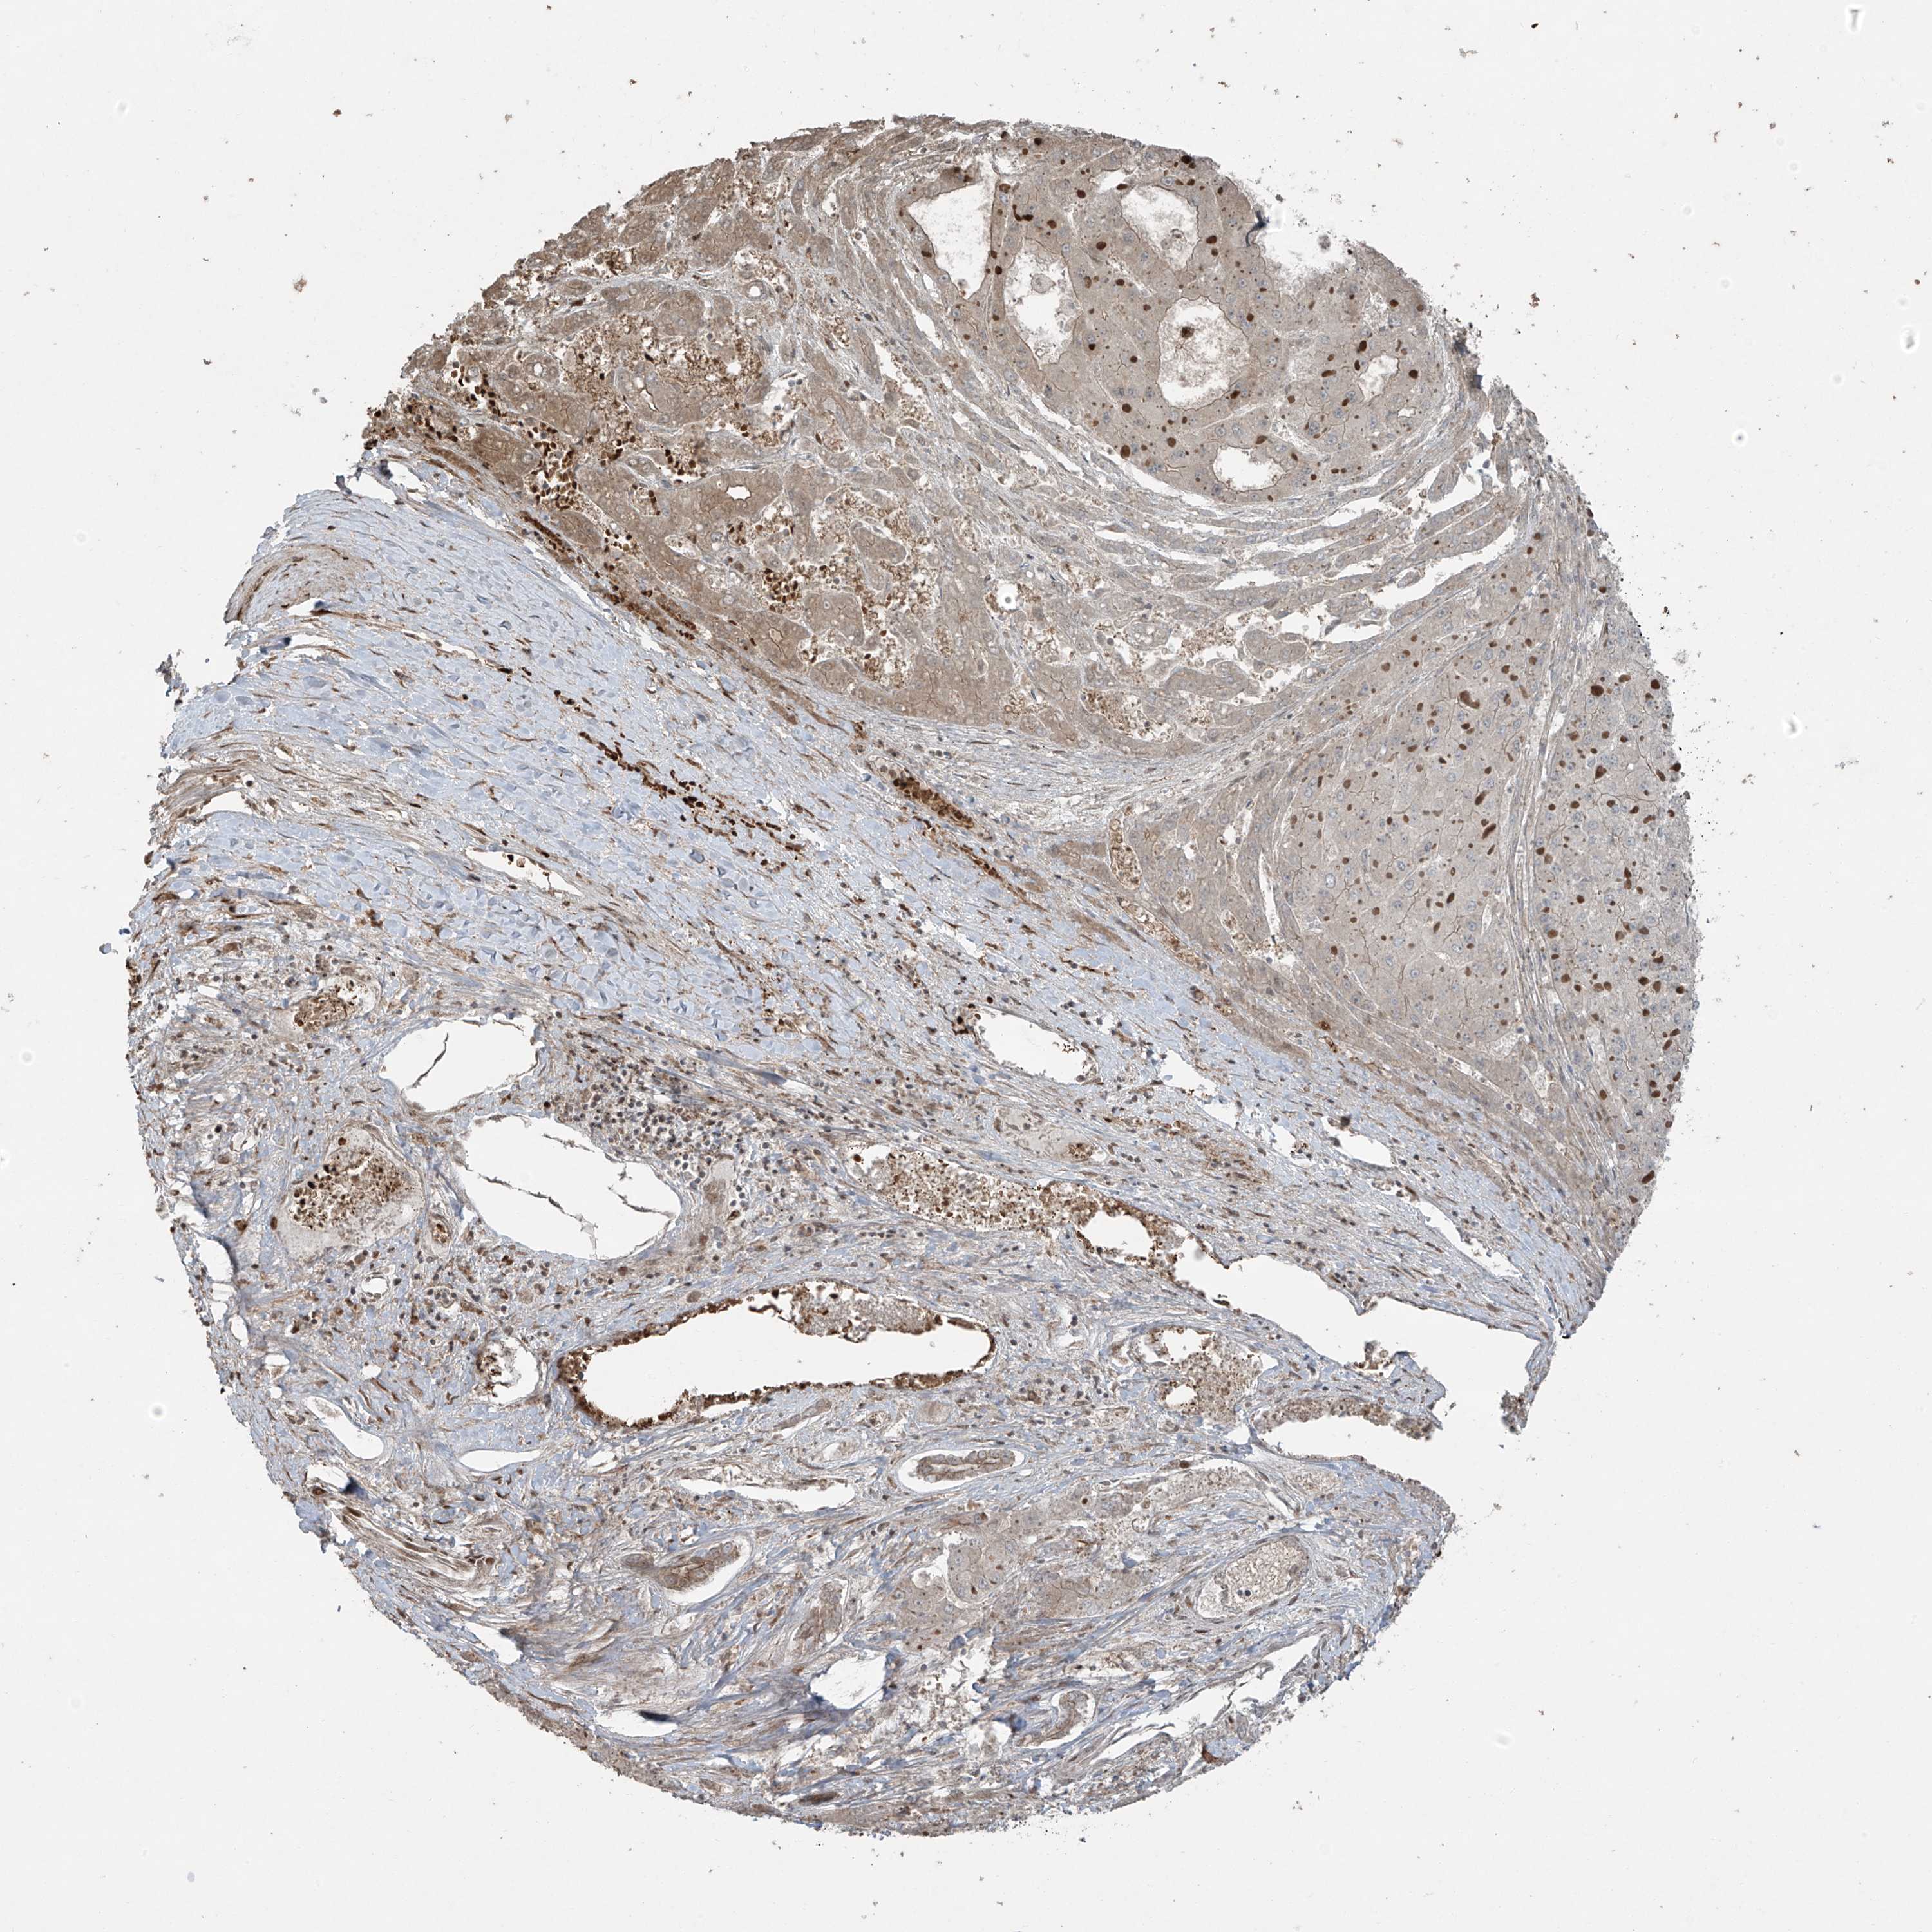

LIVER CANCER - Protein expressioni

A mouse-over function shows sample information and annotation data. Click on an image to view it in a full screen mode. Samples can be filtered based on level of antibody staining by selecting one or several of the following categories: high, medium, low and not detected. The assay and annotation is described here.

Note that samples used for immunohistochemistry by the Human Protein Atlas do not correspond to samples in the TCGA dataset.

Antibody stainingi

Antibody staining in the annotated cell types in the current human tissue is reported as not detected, low, medium, or high, based on conventional immunohistochemistry profiling in selected tissues. This score is based on the combination of the staining intensity and fraction of stained cells.

Each image is clickable and will lead to virtual microscopy that enables deeper exploration of all samples and also displays staining intensity scores, fraction scores and subcellular localization as well as patient and tissue information for each sample.

Antibody HPA035072

Staining

High

Medium

Low

Not detected

Intensity

Strong

Moderate

Weak

Negative

Quantity

>75%

75%-25%

<25%

None

Location

Nuclear

Cytoplasmic/membranous

Cytoplasmic/membranous,nuclear

Cholangiocarcinoma

Carcinoma, Hepatocellular, NOS